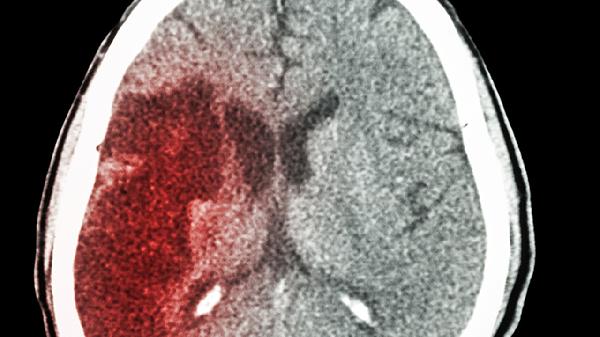

脑梗语言障碍通常无法完全自愈,但部分患者可通过康复训练改善症状。脑梗语言障碍多由大脑语言中枢受损引起,建议患者及时就医评估并接受专业治疗。

脑梗后语言障碍的恢复程度与梗死位置和面积密切相关。若损伤范围较小且未累及关键语言区域,患者可能通过大脑功能重组逐步恢复部分语言能力。早期介入语言康复训练有助于促进神经可塑性,例如进行发音练习、词汇复述和情景对话训练。同时,坚持进行口腔肌肉协调性锻炼和呼吸控制练习也能提升语言清晰度。这类患者需要长期坚持个性化的康复方案,配合认知训练来加强语言理解能力。

当脑梗导致大面积脑组织损伤或双侧语言中枢受累时,自愈可能性显著降低。这种情况下常伴随吞咽困难和认知功能障碍,需要采用器械辅助沟通或计算机语言训练系统。部分患者可能出现永久性语言功能缺损,需通过手势交流板和语音合成设备进行代偿性沟通。此类患者更需结合物理治疗与作业治疗,全面改善神经功能缺损症状。